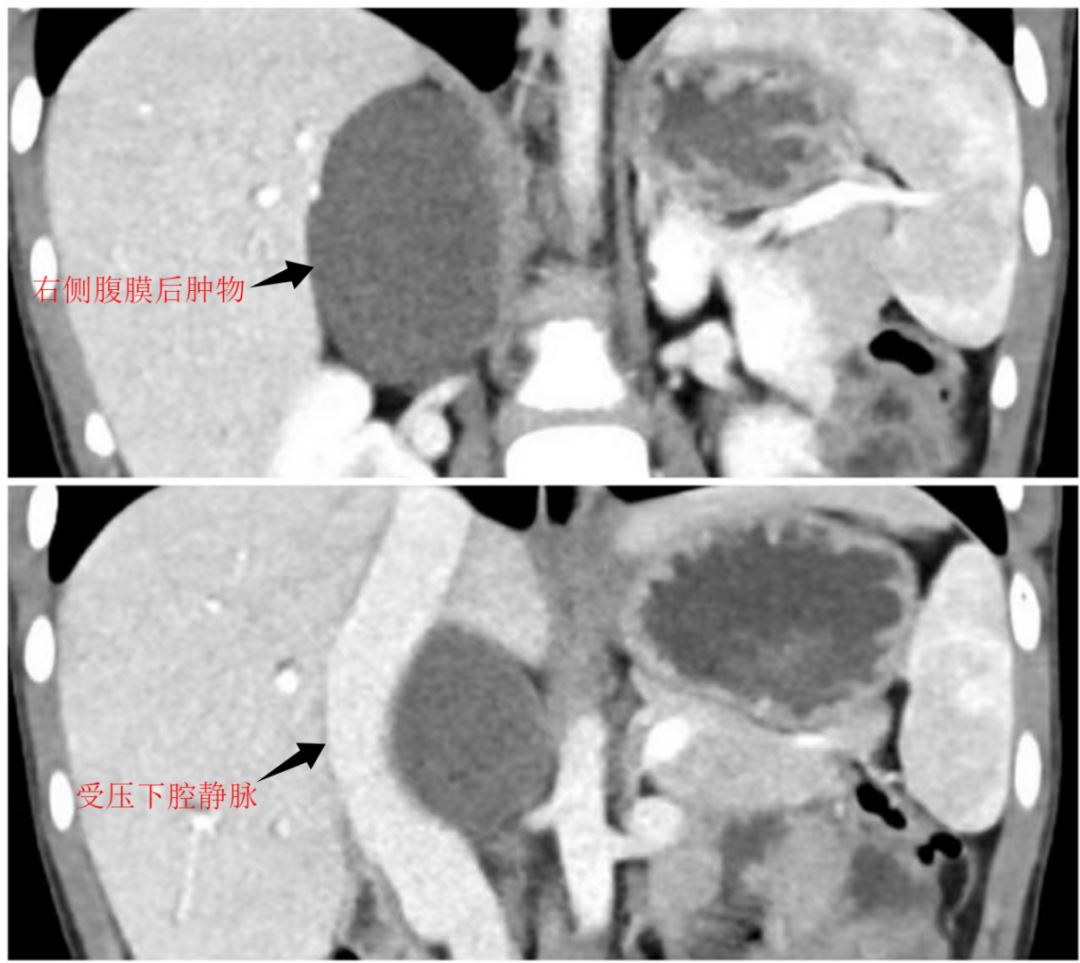

患儿右侧腹膜后巨大肿物,CT 下测量肿物达、57 mm×40 mm×65 mm,并且毗邻解剖复杂----周围脏器血管受挤压均发生不同移位:右侧肾上腺受压移位、与病灶边界不清;下腔静脉受压向右前移位,同时还毗邻肝脏邻近肝右叶明显受压呈弧形;右侧肾脏受压;胰头及十二指肠被向左前挤压移位。复杂的解剖毗邻关系以及肿物巨大的占位效应,加之不明确良恶性,若不及时干预恐引起严重的不良后果(如高血压、肠梗阻、肿瘤侵犯转移等)。然而,患儿腹腔空间狭小,肿物大且深,加之复杂的解剖关系,使得手术风险极高。

为了以最小的代价解决问题,曹振杰主任团队联合麻醉科、影像科等多学科专家,经过严谨的术前评估与讨论,最终决定采用单孔腹腔镜技术实施肿物切除。术中探查见:肿物将胆囊及肝脏向前顶起,右侧肾上腺向右侧挤压推移,下腔静脉与十二指肠被向前挤压推移。肿物系实性椭球形,质地坚韧不能推动,包绕于右侧肾上腺、右侧肾动静脉、下腔静脉及腹主动脉之间。其中右肾上腺静脉横跨肿物表面,且肿物左缘与腰大肌粘连紧密。曹振杰主任团队面对困难,精准操作、仔细分离,最终将肿物完整切除。在此过程中,团队克服了三大难关: